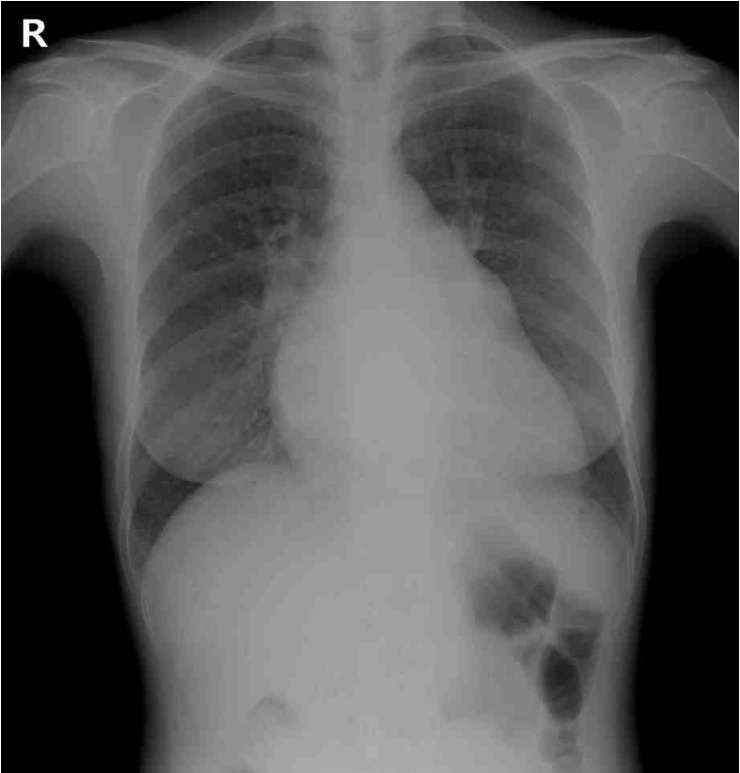

26세 여자가 2개월 전부터 숨이 차서 병원에 왔다. 계단을 오르거나 무거운 짐을 들면 증상이 심해지고 쉬면 호전된다고 한다. 혈압 104/68 mmHg, 맥박 78회/분, 호흡 18회/분, 체온 36.5 °C이다. 제1심음이 항진되어 있고 심장 끝에서 저음의 확장기 잡음이 들린다. 가슴 X선사진과 심전도이다. 심초음파검사 결과는 다음과 같다. 치료는?

CXR: Cardiomegaly

• CXR상 cardiomegaly가 확인되므로 호흡곤란의 원인은 심장성 원인임을 파악할 수 있다.